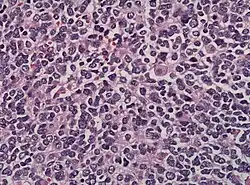

Bei der mikroskopischen Untersuchung besteht das Tumorgewebe häufig aus Zellen mit dichten Kernen, die nur wenig Zytoplasma enthalten. Charakteristisch ist die Ausbildung eines Pseudorosetten-Musters. Vereinzelt finden sich einzelne Ganglienzellen. Sollten zahlreiche Ganglienzellen vorhanden sein, kann der Tumor bereits zu einem Ganglioneuroblastom ausdifferenziert sein.